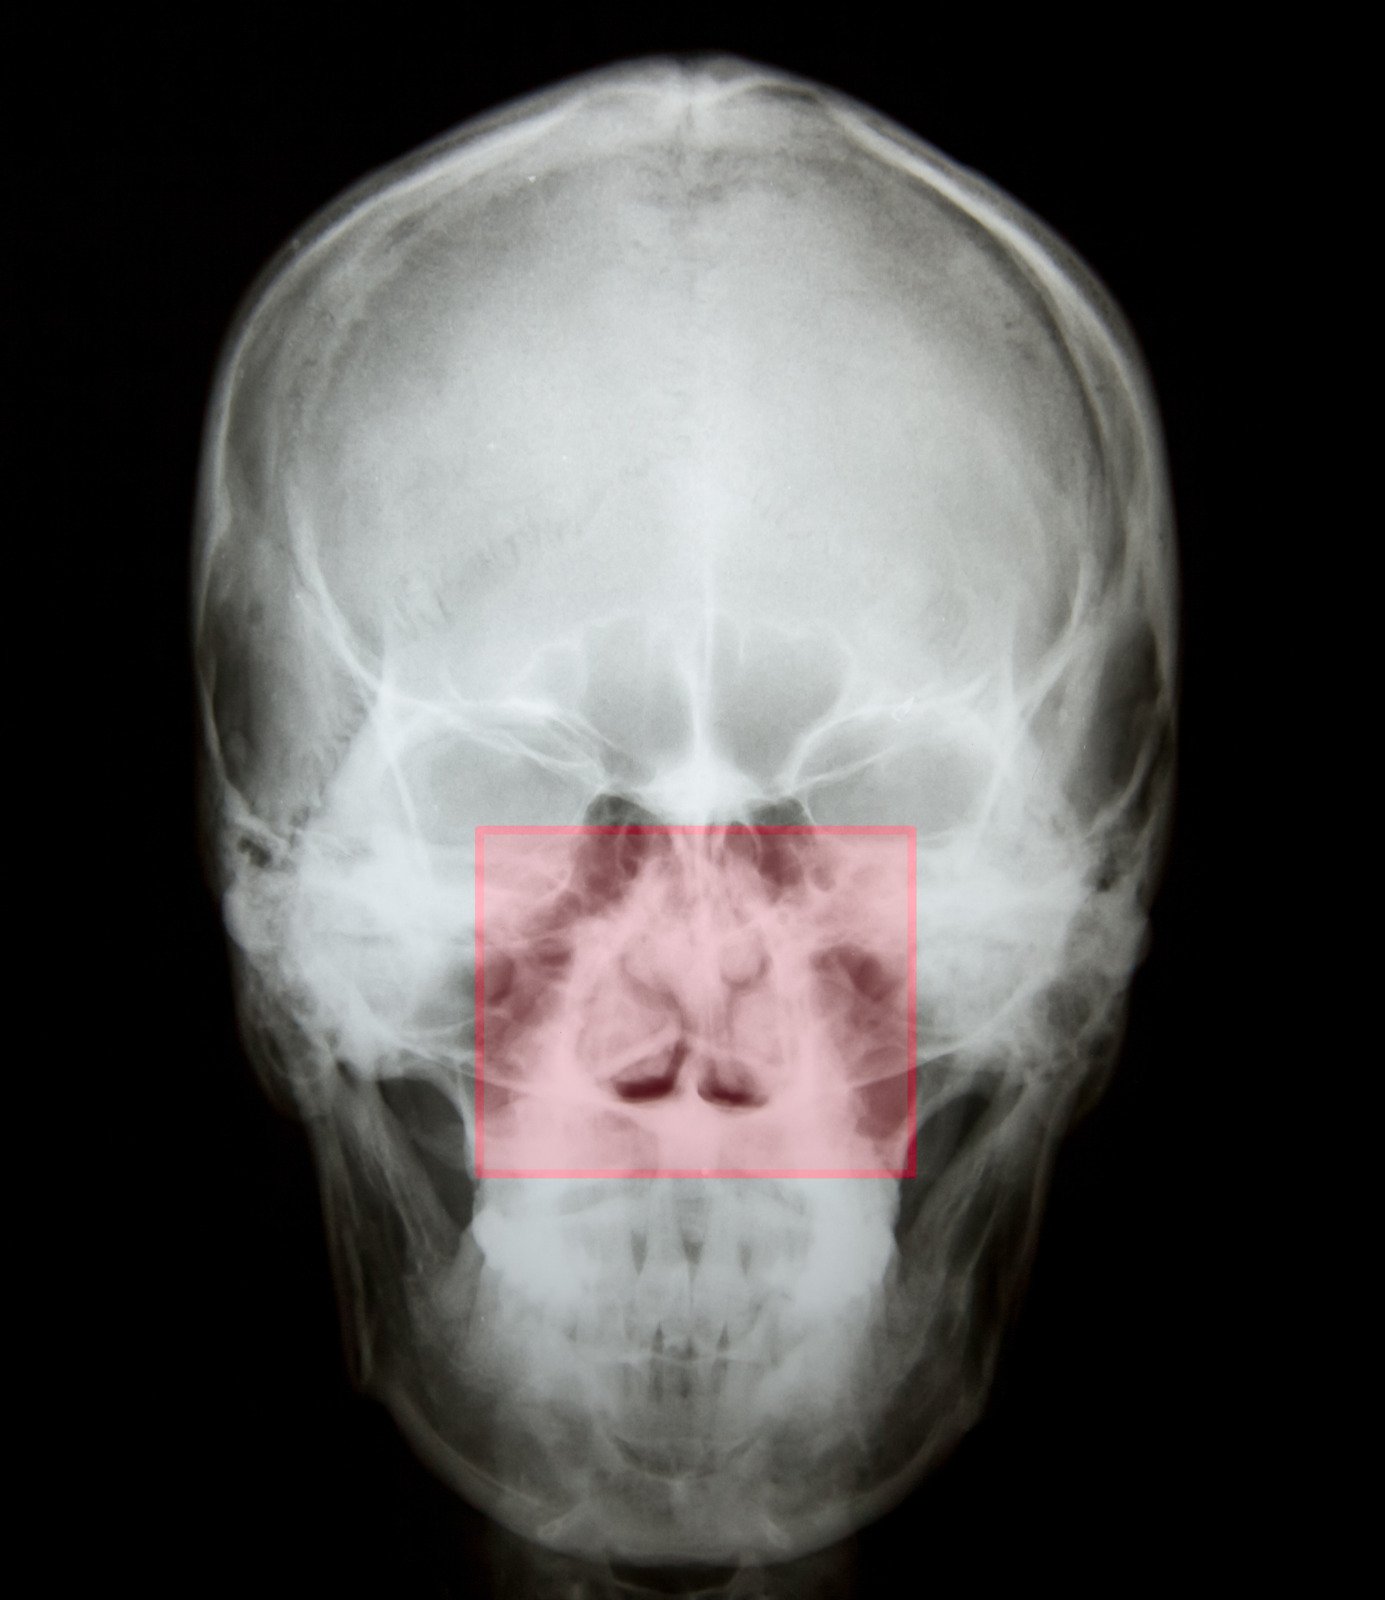

진단 검사:

비경검사(Nasal Endoscopy), CT 스캔 등을 통해 비중격의 상태와 코 내부 구조를 평가.